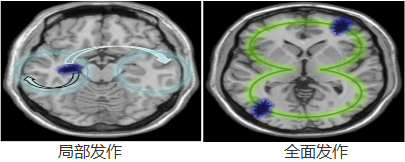

2.儿童典型局限性发作又称为简单部分运动性发作

表现为病灶对侧口角、眼睑、手指、足趾或一侧面部及肢体末端短阵性抽搐或麻木刺痛。抽搐有时可由手指至上肢扩展到对侧。症状持续数分钟以上。发作时意识不丧失。>>>怎样可以治疗?点击为您答复